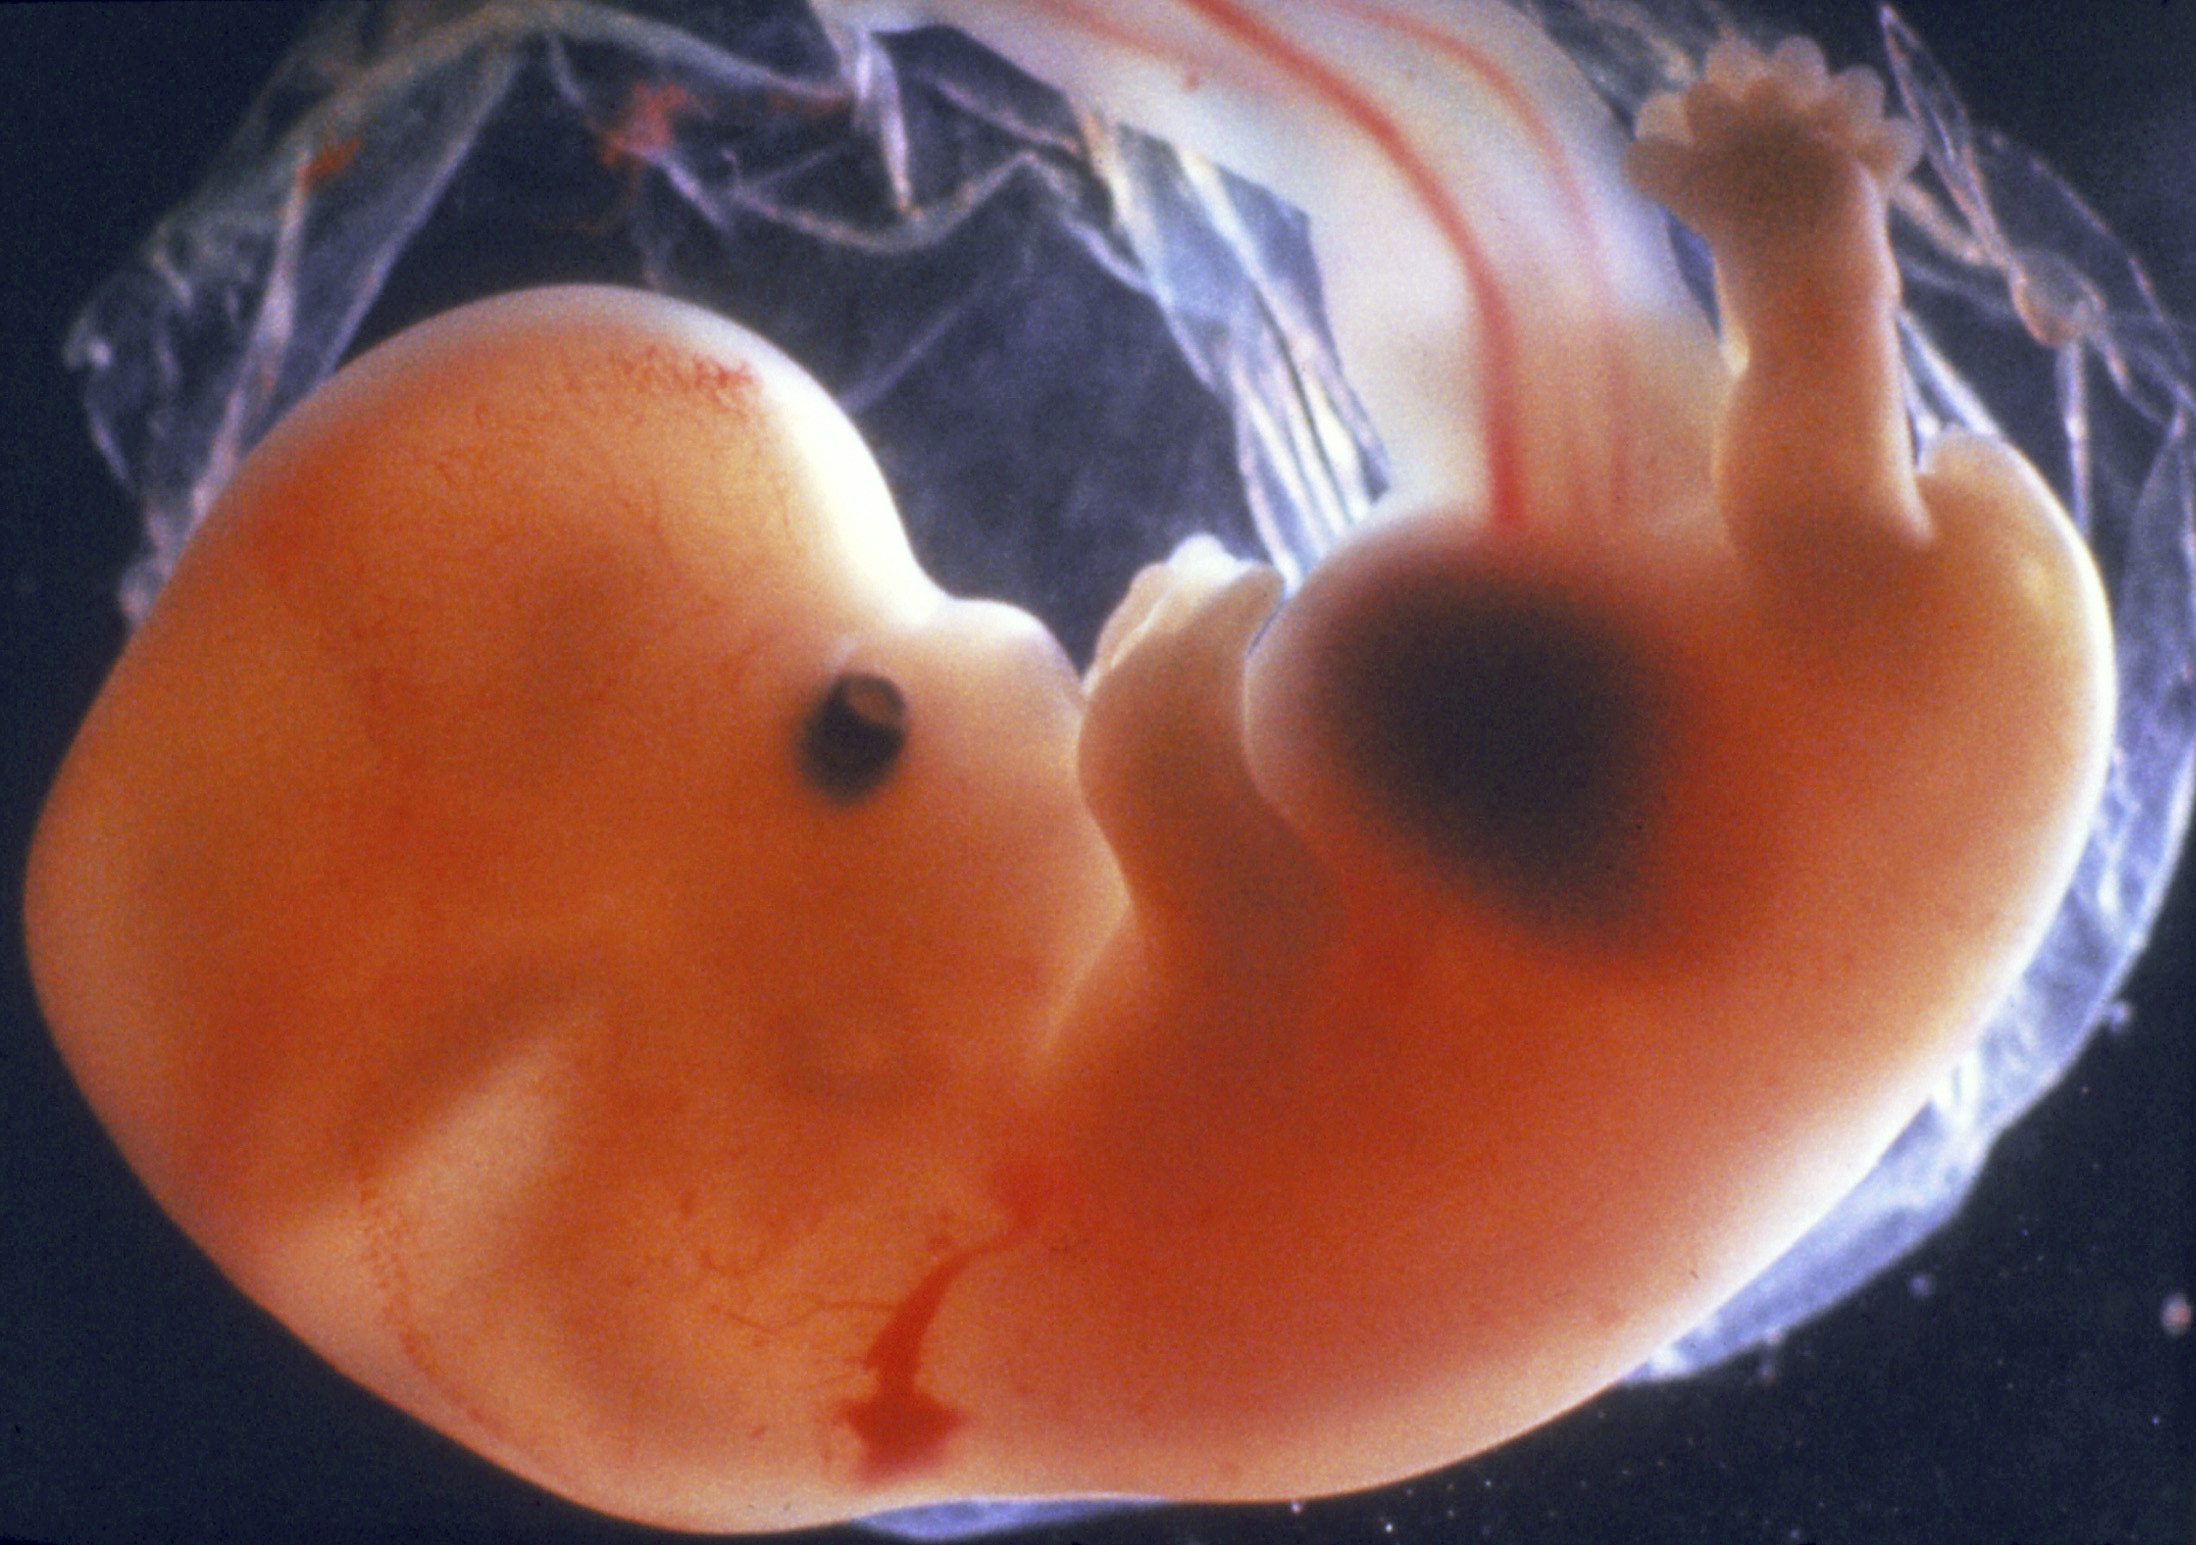

Эмбрион Леннарт Нильсон

Эмбрион Леннарт Нильсон

Эмбрион Леннарт Нильсон